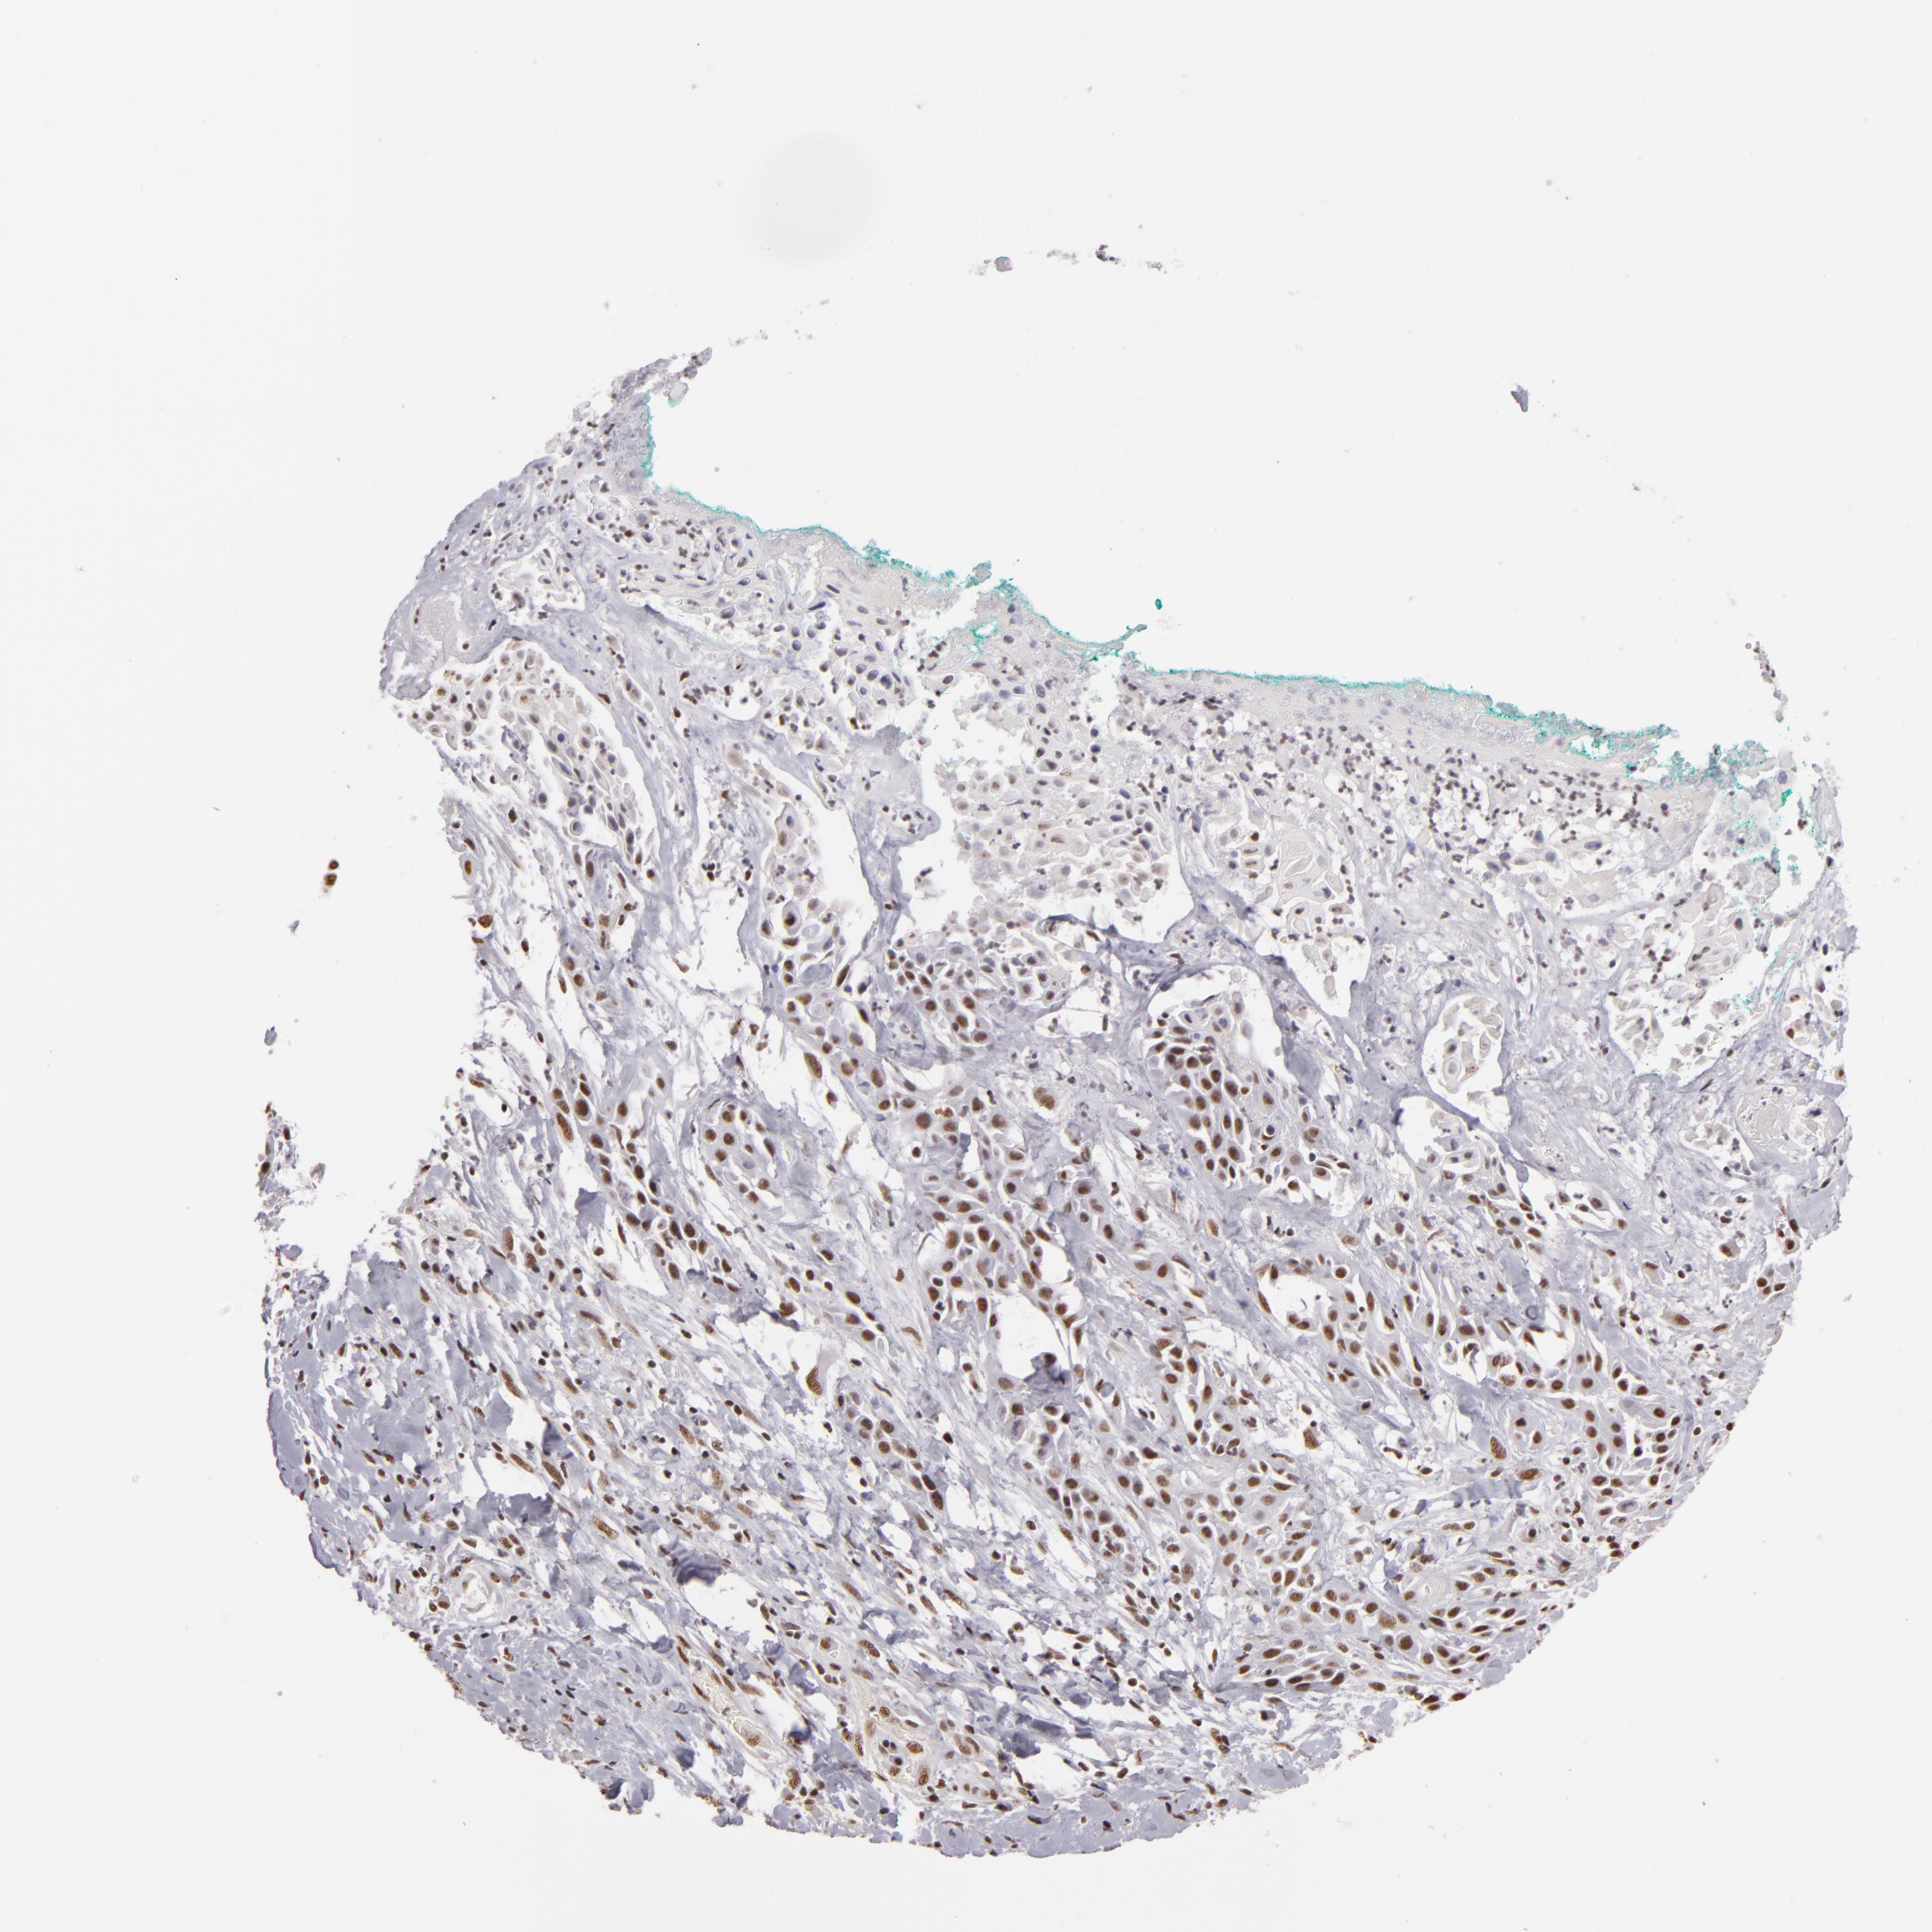

CANCER SKIN CANCER Show tissue menu

SKIN CANCER - Protein expressioni

A mouse-over function shows sample information and annotation data. Click on an image to view it in a full screen mode. Samples can be filtered based on level of antibody staining by selecting one or several of the following categories: high, medium, low and not detected. The assay and annotation is described here.

Each image is clickable and will lead to virtual microscopy that enables deeper exploration of all samples and also displays staining intensity scores, fraction scores and subcellular localization as well as patient and tissue information for each sample.

Antibody HPA001552

Squamous cell carcinoma, NOS